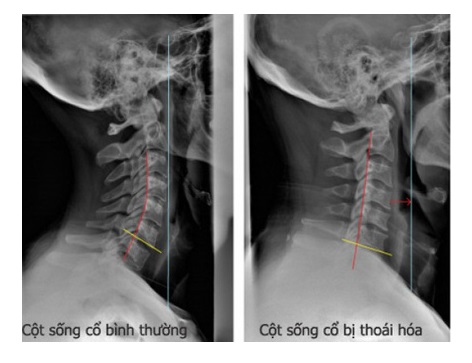

Hình chụp X-quang cột sống cổ bình thường và cột sống cổ bị thoái hóa (Ảnh: Internet)